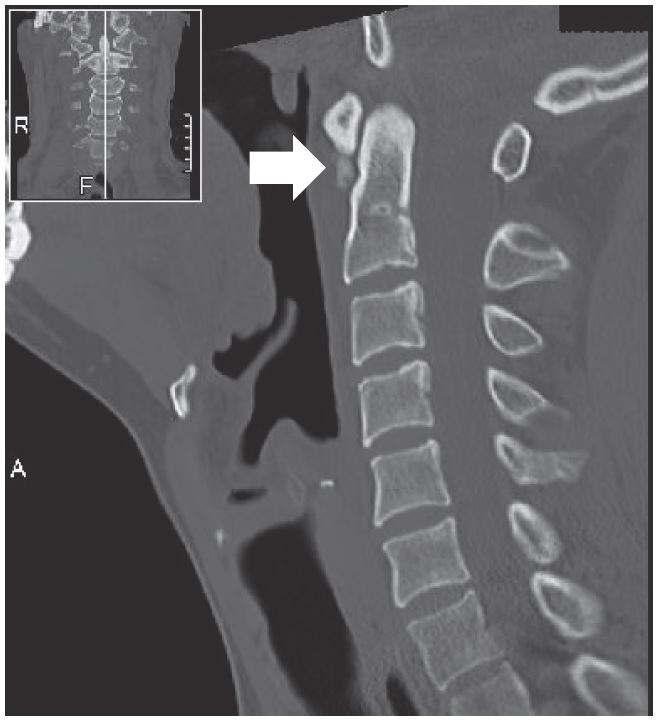

頚長筋 石灰化 (484 無料写真)

頸部痛+嚥下時痛」謎解きに有効な検査と治療 3ページ目 :日経メディカル。

CT撮らないとわからない 首が固い・回らない!治らない原因は? Crowned denssyndrome │佐藤脳神経外科豊橋MRICT│美容頭痛痛み脳梗塞認知症白玉点滴│プラセンタ。

発熱を伴う急性の頸部痛 もう騙されない!外来に現れるミミック疾患 16– 日本医事新報社。

PDFDifferential Diagnosis of Neck Pain: = Six Cases- of CalcificTendinitis of the Longus Coli Muscle。